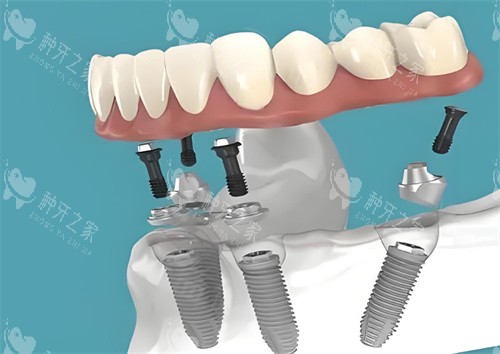

all-on-4全口种植牙模型图

全口种植牙卡通图片

全口种植牙的示意图

全口种植牙动画示意图